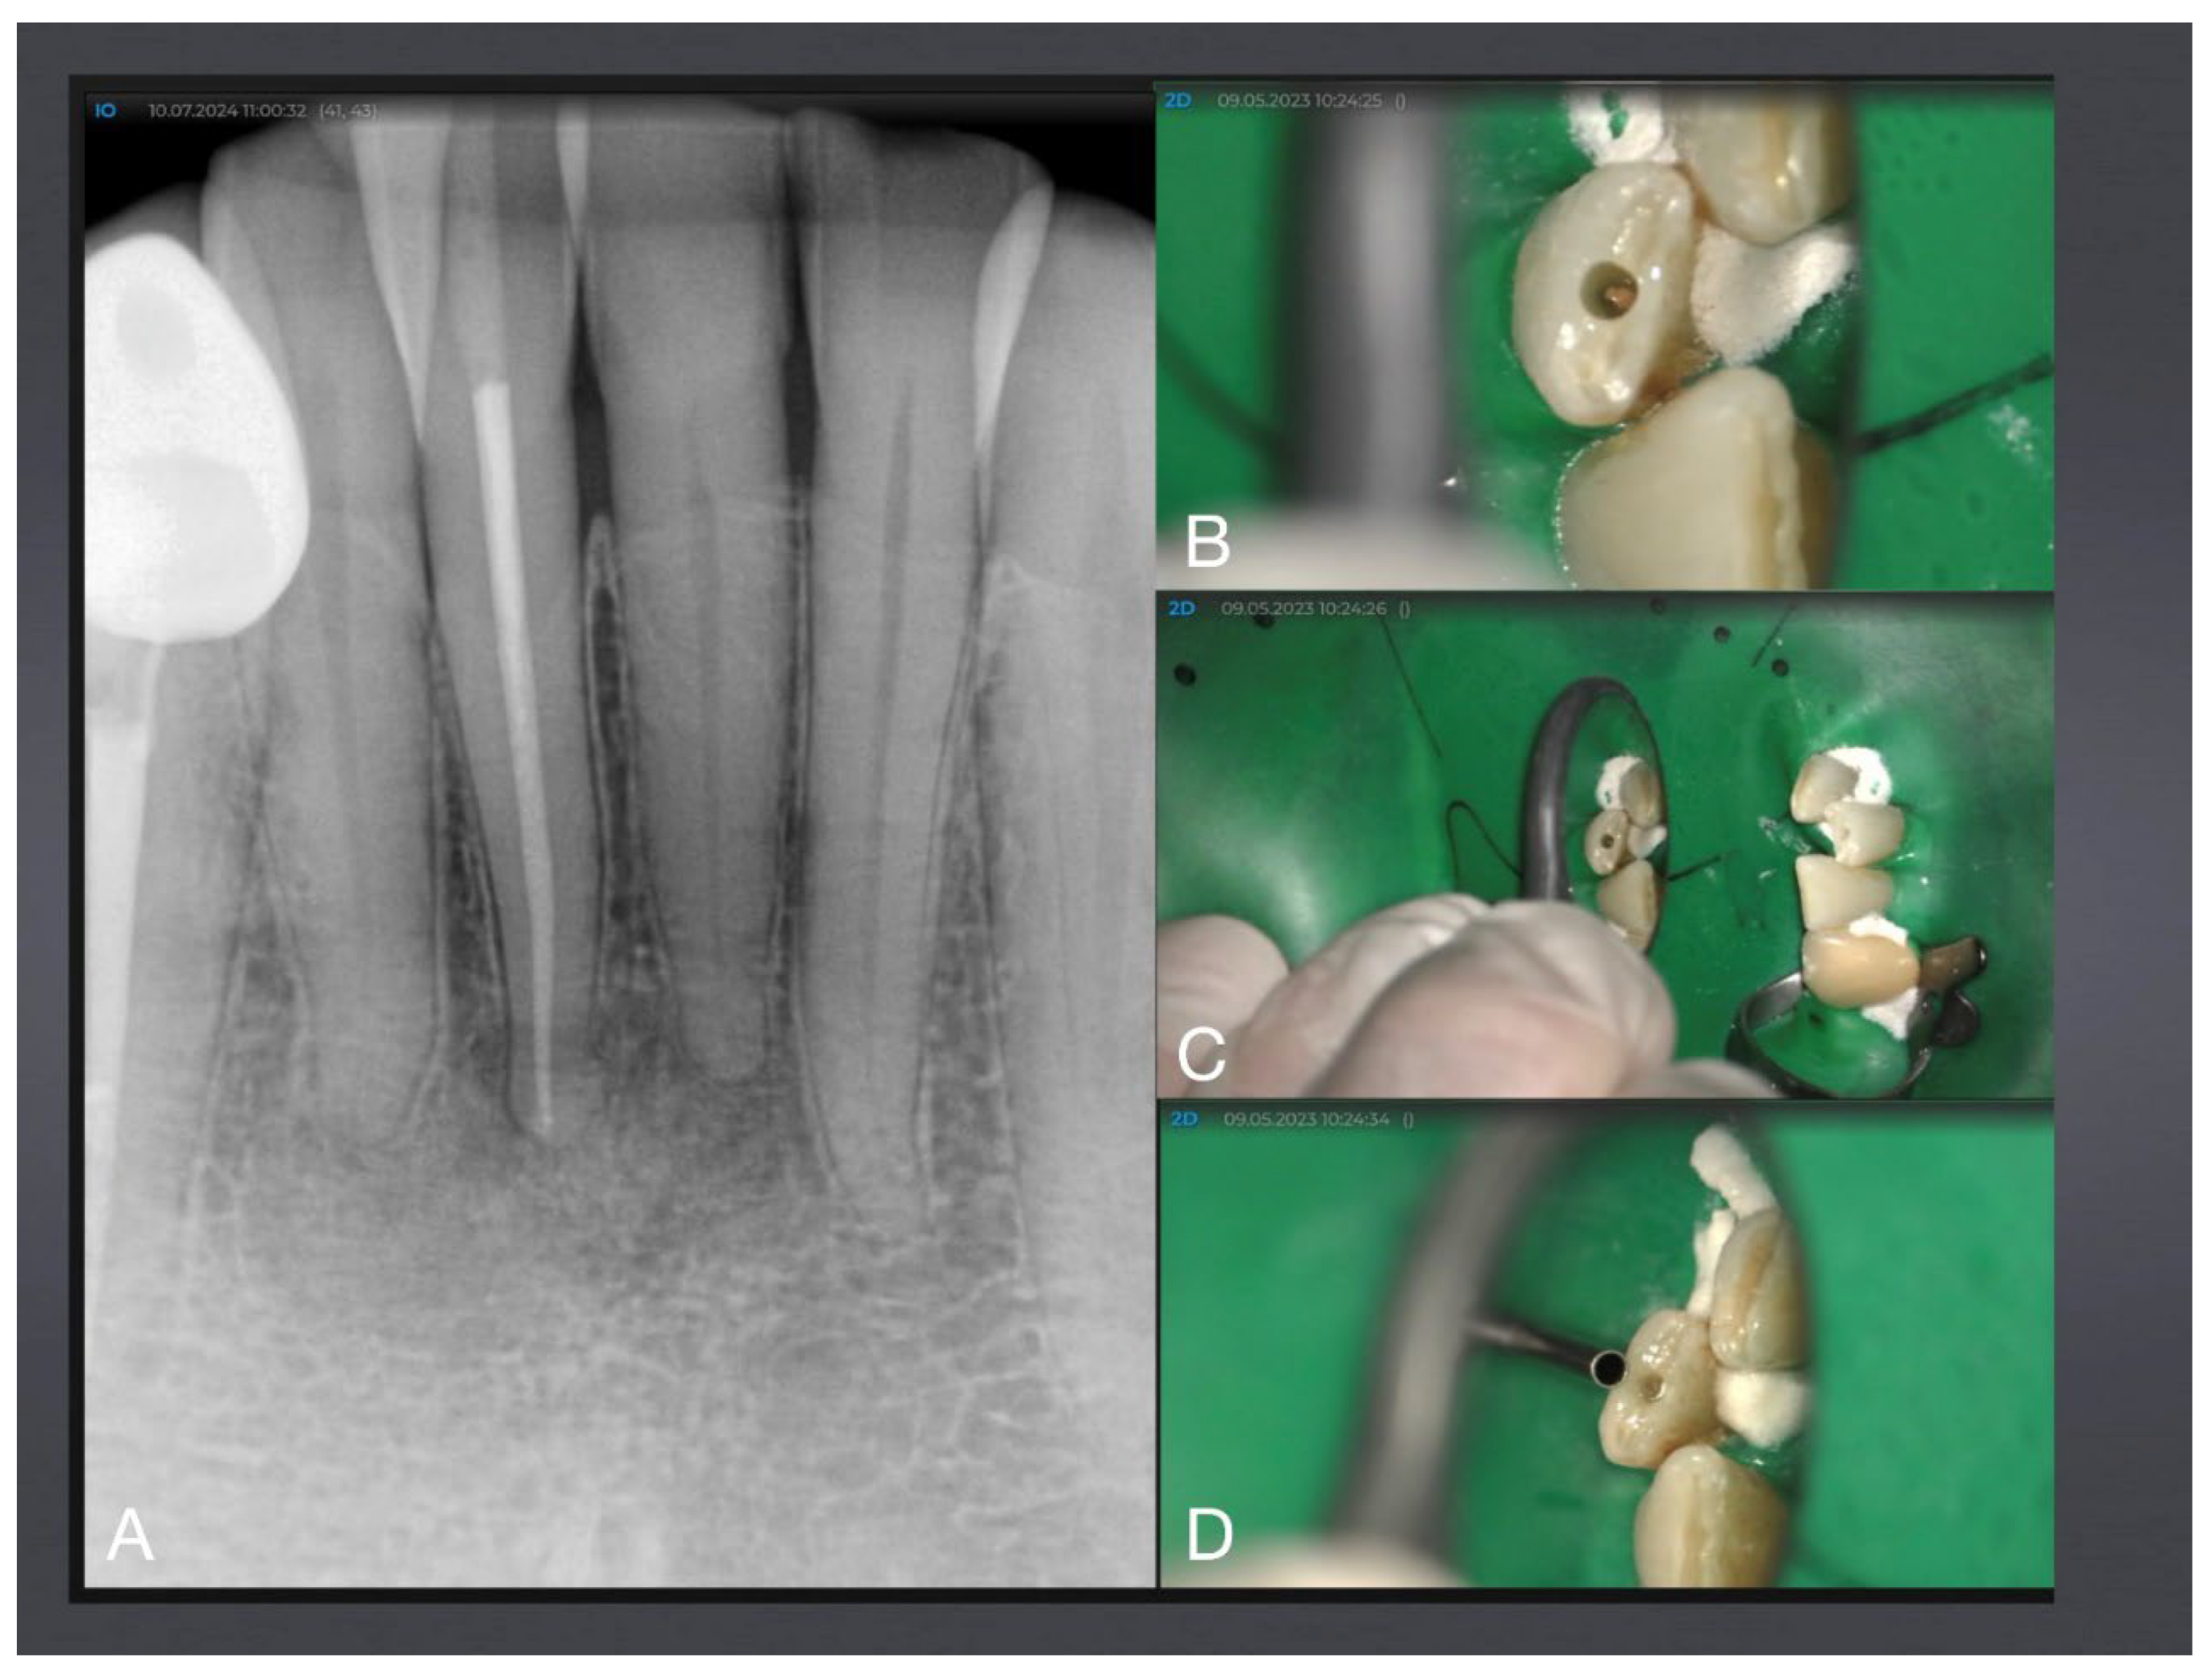

Figure 8. Mandibular molar with 15° root canal access cavity angle next to the anterior caries lesion. A: Baseline X-ray with anterior filled caries lesion and apical periodontitis. B: Access planning with SICAT-Endo guiding software. C: Dried root canals after instrumentation and disinfection. D: Root canals after filling (photographed through water). E: final X-ray after microinvasive root canal treatment via occlusal surface demonstrating preserved peri-cervical dentin (red line).